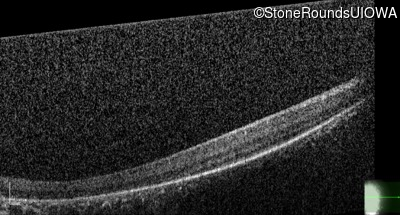

Optical Coherence Tomography - Left - Light Perception

Exemplar